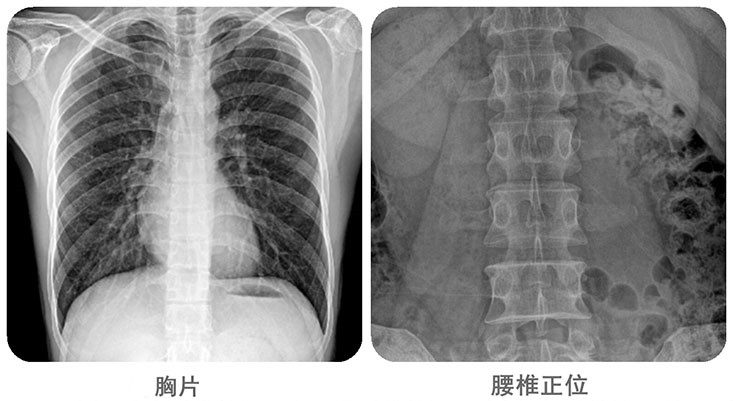

清晰影像,便于临床诊断。移动DR能够满足人体的头部、四肢、胸腔、脊柱、腰椎、腹部等全身多部位的数字化摄影需求。